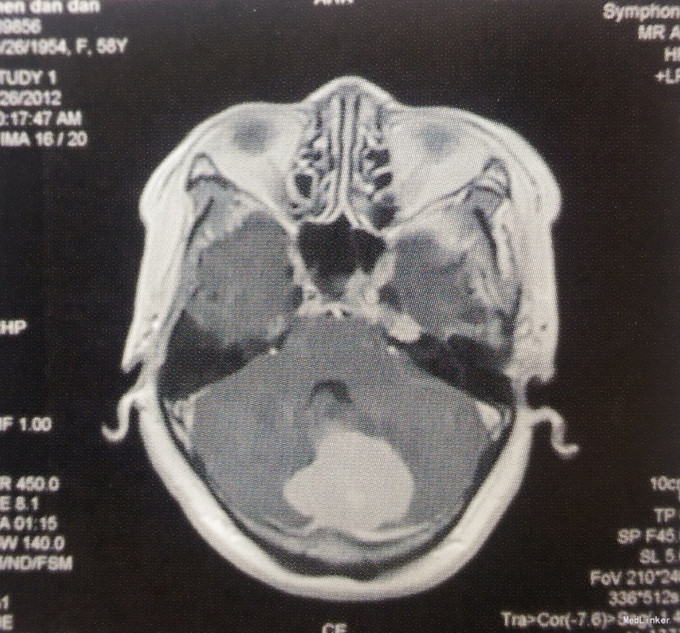

体格检查:神经系统未见阳性体征。 术前影像学检查 头颅MRI检查:小脑幕下两侧小脑半球脑外占位性病变,左侧病变为著,边界清楚,第四脑室受压变窄,幕上脑室轻度积水,增强扫描病变明显均匀强化,考虑脑膜瘤可能性大。